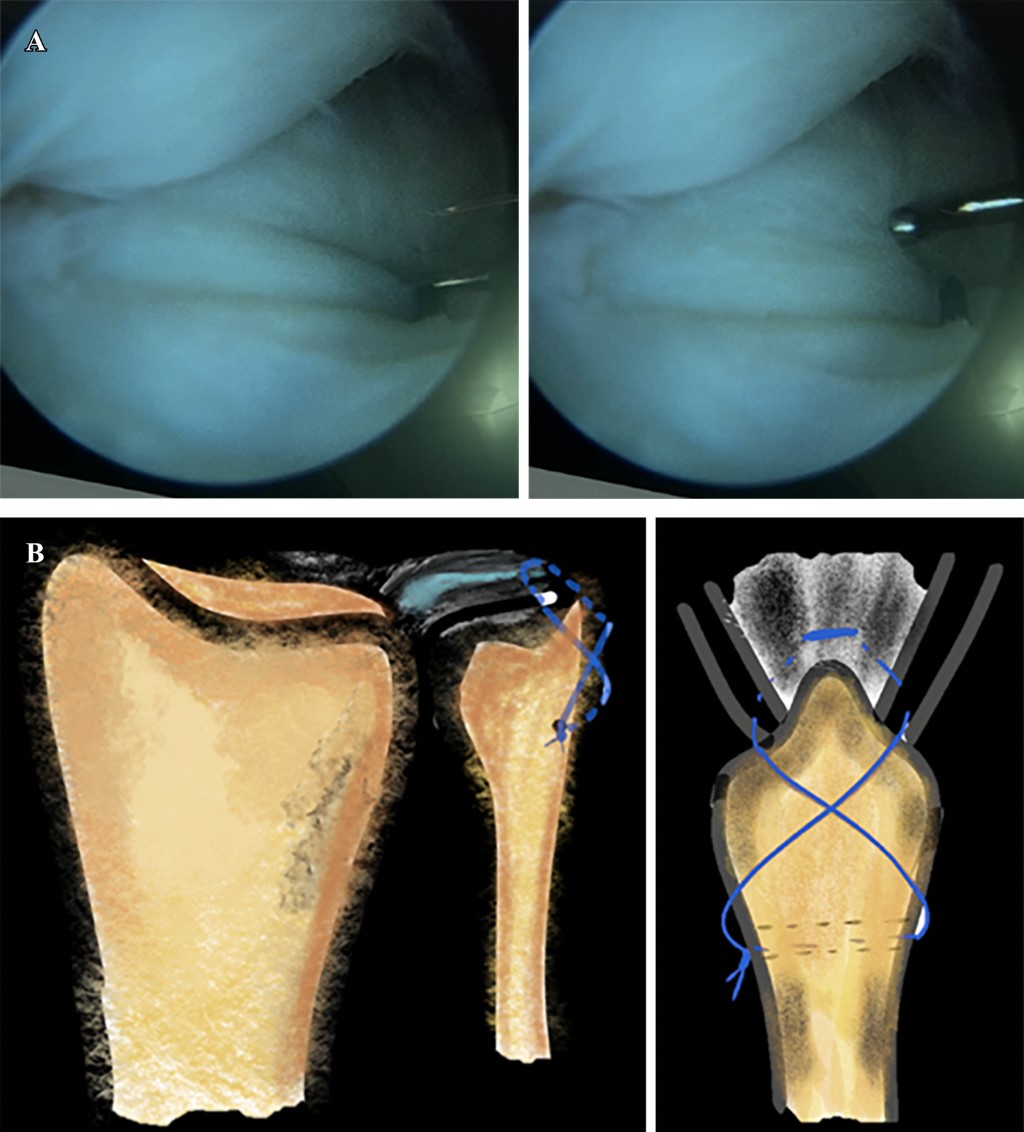

Introducción: el antebrazo puede considerarse como una articulación en sí misma donde interactúan el cúbito y el radio. Está constituida por la articulación radiocubital proximal (ARCP), la membrana interósea (MIO) con la banda medial como componente principal, y la articulación radiocubital distal (ARCD), que incluye el complejo fibrocartílago triangular (CFCT). La lesión de Essex-Lopresti (LEL) es una lesión compleja causada por una carga axial del antebrazo, que conlleva la disociación radiocubital longitudinal y la pérdida de estabilidad debido a la rotura de la MIO, la lesión de la ARCP con la cabeza del radio y lesión de la ARCD por afectación del CFCT. El diagnóstico precoz es crucial ya que el tratamiento de las lesiones crónicas plantea un importante desafío. Objetivo: describir la LEL crónica, revisar la literatura y compartir la experiencia de su tratamiento. Caso clínico: se describe el caso de un varón de 30 años que sufrió un accidente de moto en 2019. Diagnosticado inicialmente de fractura conminuta de cabeza radial derecha, fue tratado inicialmente mediante resección de la misma. El paciente visitó nuestro centro en 2023, la exploración clínica mostró dolor en muñeca y una protrusión dorsal de cúbito reductible pero inestable, sin dolor ni limitación de movimiento en el codo y antebrazo. Las pruebas complementarias, radiología simple y RMN, mostraron una varianza cubital positiva, una subluxación dorsal del cúbito a nivel de la muñeca y una lesión del CFCT, sin evidencia de ruptura aguda de la MIO. Se llevó a cabo un examen bajo anestesia y una evaluación fluoroscópica para examinar la estabilidad y el rango de movimiento del codo y la ARCD, así como la estabilidad longitudinal del antebrazo mediante tracción. Al no observarse inestabilidad longitudinal, se realizó una osteotomía de acortamiento del cúbito de 10 mm y se fijó con una placa y tornillos. De forma artroscópica, se observó la desinserción del CFCT y se reinsertó mediante una modificación de la técnica de Mantovani. Se inmovilizó con una férula de Münster. A los seis meses de seguimiento, tiene un EVA de 0 en codo y muñeca, y una flexión dorso/volar de 80º/80º, y un déficit de supinación/pronación de 10o/10o. Conclusiones: la LEL es una patología infrecuente pero desafiante para el cirujano. Las opciones terapéuticas incluyen diversas intervenciones quirúrgicas, siendo el acortamiento del cúbito con reparación del CFCT una opción viable en casos crónicos sin inestabilidad longitudinal.

Figura 2